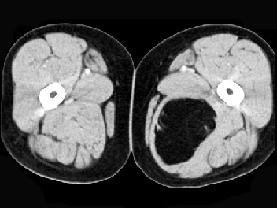

问题 女性,52岁,感左小腿肿胀两年余,活动后稍加重,不痛不热,请结合所提供的图像,选择最佳答案 ( )

选项 A、大腿囊肿 B、大腿脂肪瘤 C、大腿畸胎瘤 D、大腿平滑肌瘤 E、大腿错构瘤

答案 B